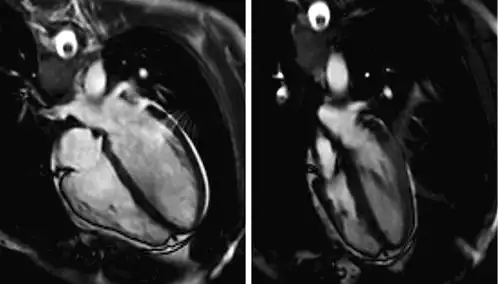

The increased intrathoracic pressures that follow GI are likely to impede venous return and induce hypotension with consequences varying from dizziness to even fainting just prior to BH diving [, ]. To give but one example: in a healthy female elite apneist, stroke volume was 92 mL and cardiac output was 4.6 L/min during control. After GI and 2-min apnea both stroke volume and cardiac output were considerably decreased to 48 ml and 3.2 L/min, respectively [] (Fig. 4).

Fig. 4

Glossopharyngeal insufflation (GI). End-diastolic four-chamber view (steady-state free precession MRI). Left: supine control. Right: after GI and 2-min apnea. Reproduced with permission from Schipke et al. [].